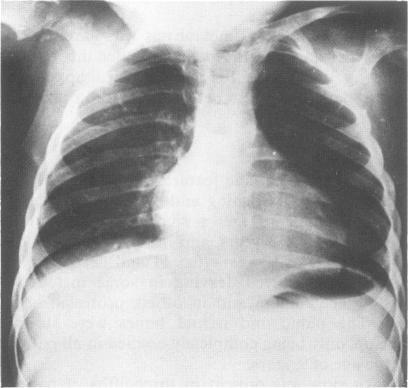

This survey reviews the diagnosis (predominantly radiological) of 32 cases of pseudoachondroplasia from 26 kindreds and illustrates the natural history and varying appearance of the disordered bone growth from infancy to adult life. In addition, an attempt has been made to detect phenotypic differences between autosomal dominant and recessive types (excluding isolated cases), analysing 10 kindreds of dominant inheritance (three in the current survey, seven from published reports) and six of recessive inheritance (three in the current survey, three from published reports). There appears to be no clinical or radiographical feature which clearly distinguishes them, but, using height as a criterion of severity, among those with autosomal recessive inheritance there was a disproportionate number of the most severely affected cases and there also appears to be very little intrafamilial variation. It is possible that pseudoachondroplasia can be subdivided into autosomal dominant mild and severe and autosomal recessive mild and severe, but full delineation must await elucidation of the basic defect at biochemical and molecular levels.

本调查回顾了来自26个家族的32例假软骨发育不全病例的诊断(主要是放射学诊断),并阐述了该疾病从婴儿期到成年期骨骼生长紊乱的自然病史及不同表现。此外,还尝试检测常染色体显性和隐性类型(不包括散发病例)之间的表型差异,分析了10个显性遗传家族(本次调查中有3个,已发表报告中有7个)和6个隐性遗传家族(本次调查中有3个,已发表报告中有3个)。似乎没有能明确区分它们的临床或影像学特征,但是,以身高作为严重程度的标准,在常染色体隐性遗传患者中,受影响最严重的病例比例过高,而且家族内差异似乎也很小。假软骨发育不全有可能可细分为常染色体显性轻度和重度以及常染色体隐性轻度和重度,但要进行全面分类,必须等待在生化和分子水平上阐明其基本缺陷。